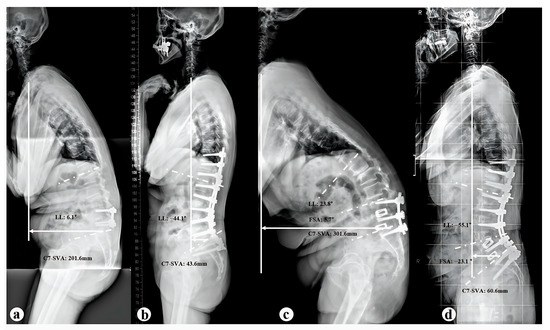

| C7SVA | C7 sagittal vertical axis |

| FSA | Fused segment angle |

| LL | Lumbar lordosis |

| C7-SVA (mm) | |||

| Preoperative | 219.8 ± 76.4 † | 293.8 ± 90.3 † | 0.026 * |

| Postoperative | 61.7 ± 66.1 † | 30.7 ± 45.5 † | 0.195 |

| LL (°) | |||

| Preoperative | 9.6 ± 19.4 † | 22.2 ± 20.5 † | 0.051 |

| Postoperative | −51.1 ± 10.2 † | −49.8 ± 8.7 † | 0.728 |

| FSA (°) | |||

| Preoperative | −7.2 ± 7.5 | 5.1 ± 8.0 † | 0.001 * |

| Postoperative | −7.8 ± 7.8 | −26.6 ± 12.6 † | <0.001 |